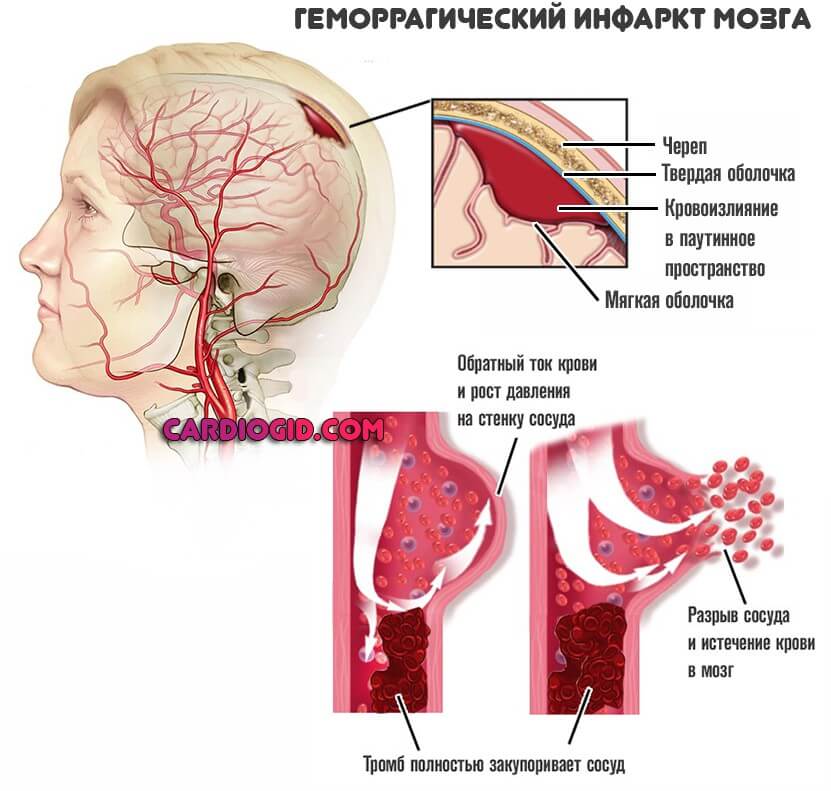

Ишемический инсульт левой стороны: симптомы и реабилитация